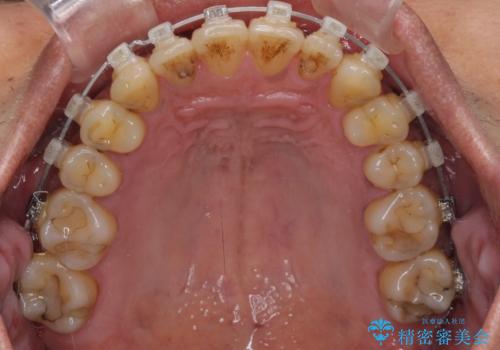

前歯のクロスバイトを改善 ワイヤー装置での非抜歯矯正

- クリアブラケット

- 骨格的な咬み合わせのズレ、前歯のデコボコとクロスバイトを気にして来院された患者様です。

骨格のズレが顕著であると診断され、マウスピース矯正では奥歯の咬み合わせが整えにくいと判断し、ワイヤー装置による矯正治療を行うこととしました。

上下の叢生は速やかに改善できましたが、右側のクロスバイトの改善に1年以上の期間を要しました。